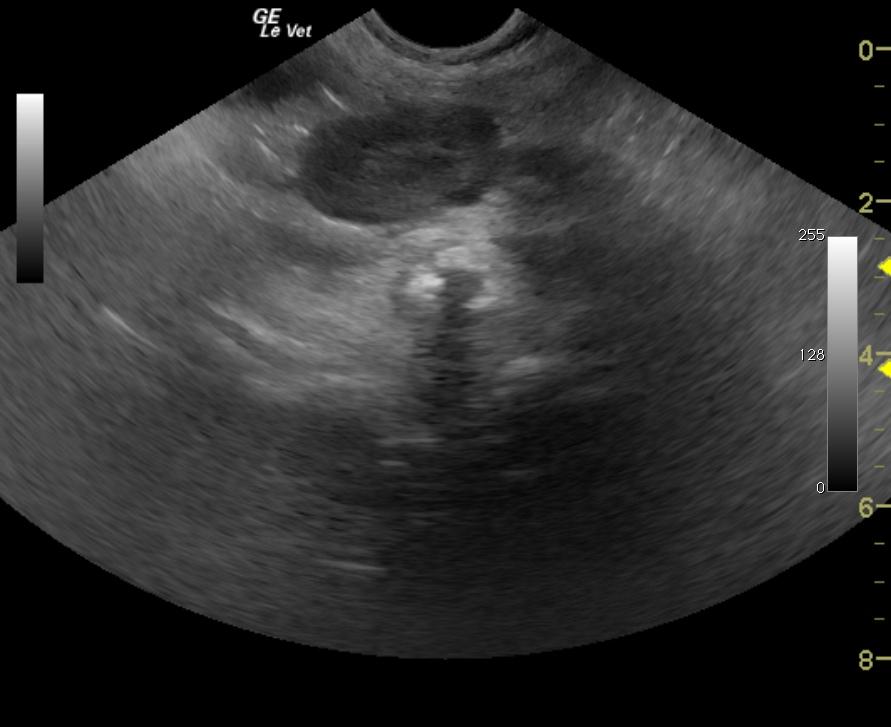

An 11-year-old MN Labrador Retriever was presented with a history of increased panting, decreased activity, diarrhea, and increased urination. Physical examination found the dog bright, alert and responsive, with an irregular cardiac rhythm, clear lungs, severely restricted range of motion of both elbows, and a normal abdomen on palpation. On rectal examination of the prostate a soft caudal margin was felt, but the entire prostate was not palpable. The only abnormality on urinalysis was 2+ proteinuria; urine culture yielded no growth. The patient was treated with Baytril and Deramaxx. Survey radiographs taken a few days later showed a mildly enlarged prostate with calcification, calcification within the sublumbar lymph node, and displacement of the descending colon.